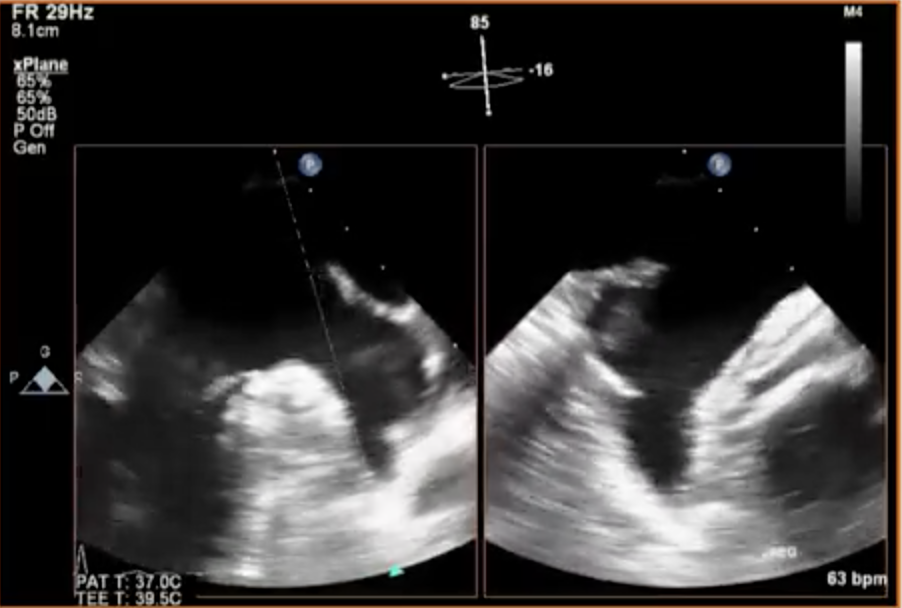

Artifact Shown Here..

An Ultrasound Beam has a Central BEAM as well as Side Beams (side lobes). if you have a bright reflector in the path of the side-lobe the machine will interpret it to be in the center.

Benefit of Harmonic Imaging is that is suppresses the fundamental frequenceis and clutter/side lobe artifacts are easily suppressed.